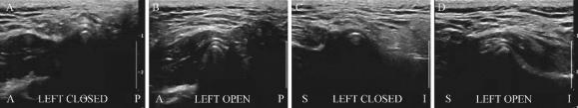

结合谢阿姨的身体情况,胡旭与医学影像科、超声科、康复医学科进行了多学科会诊,采用了省内首创的B超引导下颞下颌关节腔注射治疗结合手法治疗 。5分钟后,谢阿姨从来医院前的2.3cm的张口度增大到3.6cm的张口度 。后续配合居家的运动疗法巩固治疗效果,定期门诊复查,后续张口度维持在4.0cm以上,谢阿姨终于可以开心的正常吃饭了 。接下来需要定期复查,能保持正常功能前提下,就不需要手术了 。

“传统的关节腔注射,主要凭医生的经验和手感,文献报道,注射成功率在80%左右,我院目前采取的B超引导下颞下颌关节腔注射治疗,在无创的B超引导下,做到了有的放矢,精准可靠,成功率接近100%,在保证临床治疗有效的前提下,大大提高患者治疗的体验感 。”胡旭介绍 。1颞下颌关节是什么?它是位于耳前的一个小关节,它将颅骨与下颌骨连接起来 。正是这个关节使得下颌可以进行运动和行使功能,是全身运动最频繁的关节 。颞下颌关节是一个球窝状关节,其球状部分称髁突,窝状部分称关节窝 。在髁突与关节窝之间有一个软骨构成的关节盘,用于缓冲压力并协助髁突进行张闭口运动 。